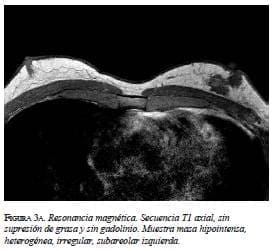

En la mamografía (figura 1a y 1b) se demostró una masa densa, irregular, de 3 x 2 cm en la región subareolar izquierda. Por ultrasonido (figura 2) se confirmó la pre-sencia de una masa sólida, hipoecoica e irregular. En la resonancia magnética (figura 3 a, b y c) se observó una masa hipercaptante, heterogénea, irregular, subareolar izquierda, de 3,5 x 2,5 cm, con curva de realce sospe-chosa tipo III. En todas las modalidades diagnósticas la lesión se clasificó según el sistema de datos y registro de imagen de mama (BI-RADS), como una lesión categoría V: altamente sospechosa de malignidad.